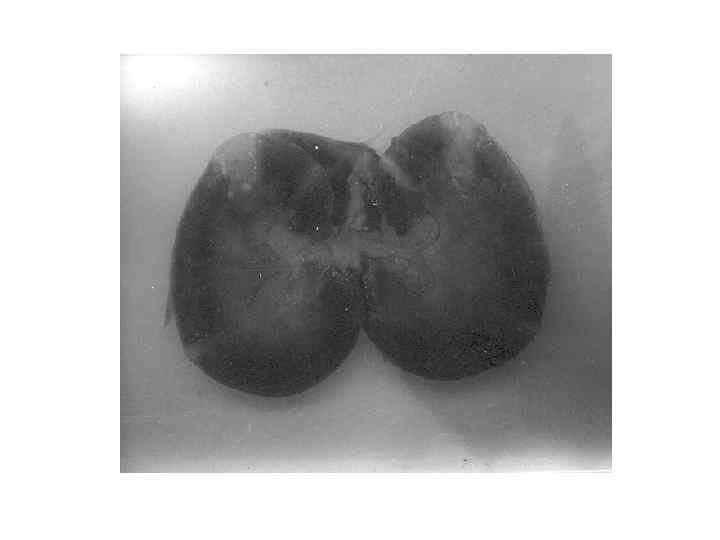

Апостематозный нефрит Карбункул почки

Абсцесс почки

• Органы мочевыделения: Почки на обычном месте, дряблые, общей массой 450, 0 г. Размеры: правая 13 х5, 5 х4, 5 см, левая – 13 х5 х4 см. Параметрий отечный, бледно-желтоватый, блестящий. Капсулы тонкие, легко снимаются с обнажением светло-сероватой поверхности. Последняя гладкая. При этом в левой почке множество желтоватых очажков не более 0, 1 см в диаметре. В среднем сегменте в основании пирамидок очажки сливаются в участок 2, 5 х2 см. Структура пирамидок нечеткая, сосочки уплощены, своды малых чашечек сглажены. Чашечки, лоханки и верхние 2/3 мочеточников расширены до 2, 5 -3, 5 см по периметру, содержат мутную мочу (слева с примесью фибрина). Стенки их истончены, слизистые оболочка тускловатые, гладкие, с расширенной сосудистой сетью. Двухстороннее искривление и извилистость мочеточников. Нижние их трети спавшиеся, с обычным диаметром. Устья свободные. Камней на протяжении мочевыводящих путей не выявлено. Анатомическая проходимость сохранена. В большей степени все изменения выражены в левых мочевыводящих путях. В мочевом пузыре катетер с баллончиком и около 30 мл кровянистой мочи. Слизистая оболочка мочевого пузыря отечная, полнокровная, с мелкоочаговыми кровоизлияниями в области мочевого треугольника. Кровоизлияния распространяются на слизистую оболочку короткой, проходимой уретры. Распределение почечных сосудов обычное, добавочных сосудов нет. • Внутренние половые органы: Влагалище широкое, эластичное с синюшной, отечной поперечно-складчатой слизистой оболочкой. Варикозного расширения вен не обнаружено. Своды сглажены. Матка 17 х12 х8 см, с сформированным нижним сегментом. На передней поверхности нижнематочного сегмента наглухо ушитая операционная рана с состоятельным непрерывном швом, прикрытым листками пузырно-маточной складки. Шейка матки гладкая, синюшная, отечная, без разрывов. Наружный зев и цервикальный канал спавшиеся. Полость матки расширена, содержит немного жидкой темной крови. Плацентарная площадка на передней стенке тела матки, спавшаяся. Плацентарной ткани и оболочек не обнаружено. Миометрий однородный, мягкий, серо-розовый, толщиной до 3, 5 -4 см. Повреждений стенок матки нет. Трубы тонкие, узкие, извитые. Яичники 3, 5 х3 см, белесоватые, мелкозернистые с поверхности. В правом яичнике желтое тело около 2, 5 см с кровоизлиянием.

• • Органы внутренней секреции: Щитовидная железа не увеличена, эластичная, без узлов, светло-серожелтоватая. Надпочечники тонкие, треугольные. Корковый слой надпочечников желтоватый, мозговой – темно-коричневый, кашицеобразный. Органы кроветворения: Селезенка гладкая, дряблая, весом 313 г. При разрезах темно-красная, с умеренным соскобом пульпы. Лимфоузлы разных локализаций не увеличены, однородные, бледно-розовые, эластичные. Кроветворный костный мозг грудины не исследован, т. к. не было показаний. Органы пищеварения: Желудочно-кишечный тракт проходим. Структура слизистых оболочек типичная. В желудке интубационная трубка и пищевые массы с темно-зелено й желчью. В тонкой кишке кашицеобразный зеленовато-коричневатый химус, в толстой кишке – оформленные каловые массы. Червеобразного отростка нет. На слепой кишке едва заметный рубчик. Печень весом 2138 г, дряблая, гладкая, с острым передним краем. При разрезах печень светло-коричневая, с диффузными расплывчатыми желтоватыми участками. В желчном пузыре густая темно-зеленая желчь. Отек стенки желчного пузыря. Желчные протоки проходимые. Поджелудочная железа серо-розовая, дольчатая, эластичная. Бактериологическое: Кровь из периферических вен верхних конечностей и «ткань левой почки» из области апостемы – выделены клебсиелла и энтерококк (результаты бак. анализов от 26. 05. 08 г. прилагаются). Патогистологическое: Послед (исследование № 9898 от 29. 05. 08 г. ): плацента зрелая. Хроническая компенсированная плацентарная недостаточность. Отек пуповины, плацентарный децидуит, склероз сосудов ворсин, дефицит синцитиальных почек, ангиоматоз ворсин, интервиллузит, стазы в межворсинчатом пространстве и сосудах ворсинок. Ребенок угрожаемый по ВУИ и ППЦНС, у матери возможно развитие эндометрита. Почки: В правой – отек интерстиция, скудная лейко-лимфоцитарная инфильтрация, в левой – на фоне интерстициального отека множественные диффузно-очаговые лейкоцитарные инфильтраты с примесью макрофагов, разрушением нефронов, лейкостазами в мелких сосудах, скоплениями лейкоцитов в просветах канальцев; в обоих почках: малокровие клубочков при относительном полнокровии сосудов пирамидок, расширение просветов капсул Шумлянского-Боумена и извитых канальцев, скопления в канальцах белковых масс, слущенного нефротелия, свежих и гемолизированных эритроцитов, часть прямых канальцев подвержены кистозной трансформации по типу «щитовидной почки» , склероз сосудов. Мелкоочаговый кальциноз в области сосочков, некроз эпителия извитых канальцев. Мочевыводящие пути (чашечки и лоханки): атрофия переходного эпителия, склероз и выраженный ангиоматоз подслизистого слоя, атрофия мышечной оболочки с нарушением дифференцировки мышечных пучков. Интрамуральные вегетативные ганглии и нервные волокна сохранены. Отек и полнокровие адвентиции и прилежащей жировой клетчатки. В нижней трети мочеточников умеренная гипертрофия мышечной оболочки. Мочевой пузырь: полнокровие и отек слизисто-подслизистой оболочек, кровоизлияния. Очаговая десквамация переходного эпителия. Мышечная и адвентициальная, а также серозная оболочка – интактные.